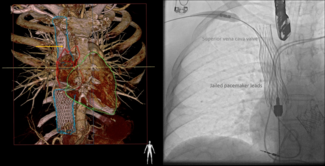

An elderly woman presented with worsening shortness of breath for a duration of 3 days. She had a history of provoked deep vein thrombosis of the right lower limb with sub-massive pulmonary embolism, for which she was on oral anticoagulant...